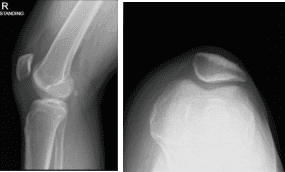

He has been complaining of knee pain despite conservative management in the form of physical therapy and anti-inflammatory medications. The patient presented X Ray for his right knee that showed no significant degenerative changes. There are no fractures.

Right knee X-ray complete with Patella